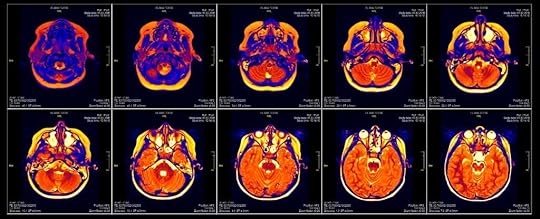

النبضات الكهربية هى ما يتحكم فى العقل البشرى

الأفكار والعواطف والمخاوف هى أختلافات فى تركيز الصوديوم والبوتاسيوم

عبر غشاء يصنع فارقا فى الجهد الكهربى مصدرا الاشارة العصبية

تجربة مجنونة لقراءة الأفكار للدكتور ّبودونّ خبير فسيولوجيا الأعصاب

من أجل التحكم والسيطرة على مشاعر وأفكار البشر

لكنها بلا مبادئ؛ فينقلب السحر علي الساحر فى النهاية

ويتحقق الانتقام الإلهى بنفس السلاح